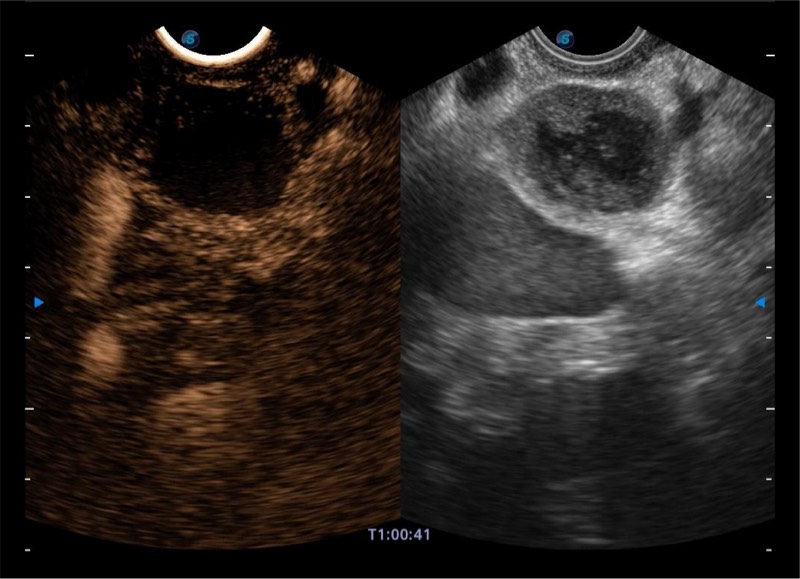

基于二十年的超声技术积累,银河集团官网提供了最新一代的独立超声主机,在提供高质量图像的同时满足多学科使用。具备常见多普勒技术并提供弹性成像、声学造影等高端影像技术。新一代传感器具有更强的抗干扰能力并减少图像伪影。